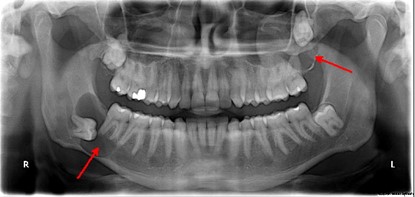

Çenelerde, dişten kaynaklanan ya da bağımsız olarak oluşan çeşitli kistler bulunabilir. Bu kistler bazen hastalar tarafından fark edilmeden oldukça büyük boyutlara ulaşabilir. Bu nedenle düzenli diş hekimi kontrollerinde panoramik diş röntgeni çekilmesi önerilir.

Çene kistleri genellikle diş kaynaklıdır ve diş kökü etrafında oluşur. Tedavi edilmedikleri takdirde büyüyerek ciddi sorunlara yol açabilirler. Diş kökünde kist bulunan hastalarda, sadece dişin çekilmesi yeterli bir tedavi olmaz. Kist kemik içerisinde bırakıldığında büyümeye devam ederek daha büyük problemlere neden olabilir. Bu durumda birden fazla dişin çekilmesi gerekebilir. Bu nedenle, kistik yapılar tespit edildiğinde cerrahi yolla tamamen temizlenmelidir.